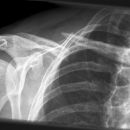

Claviculafraktur im mittleren Drittel